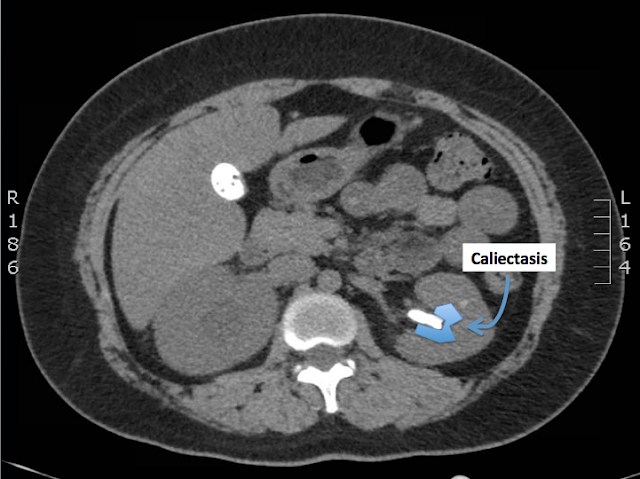

There is also a large staghorn calculus in the mid-to-upper pole of the left kidney, associated with severe left upper pole caliectasis.